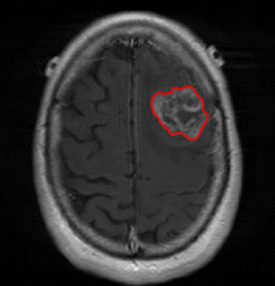

(a) Input images (b) Semantic Labels (c) Seg-Net+EG-CNN (d) Seg-Net

We argue that the sub-optimal paradigm of processing different abstractions within a single CNN pipeline can be remedied through the effective processing of information in a structured manner. Consequently, we devise strategies for disentangling the edge and texture information within a single training pipeline. Figure 2 illustrates how our proposed module, dubbed EG-CNN, can be paired with any existing CNN encoder-decoder to improve segmentation quality near intensity edges. We have applied our EG-CNN to the tasks of brain and liver tumor segmentation in medical images (Figure 3).